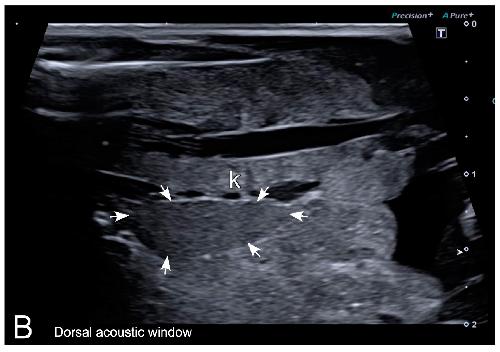

Sex Determination in Two Species of Anuran Amphibians by Magnetic Resonance Imaging and Ultrasound Techniques. , Ruiz-Fernández MJ, Jiménez S, Fernández-Valle E, García-Real MI, Castejón D, Moreno N , Ardiaca M, Montesinos A, Ariza S, González-Soriano J., Animals (Basel). November 18, 2020; 10 (11):